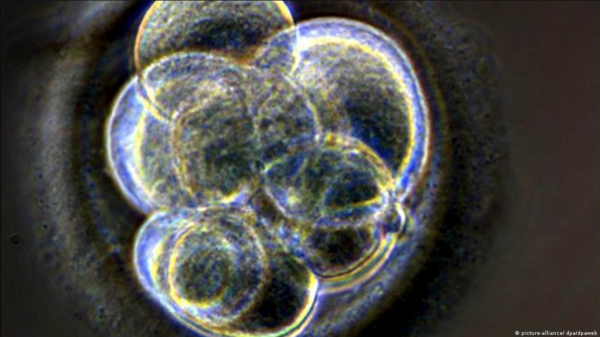

Según la Organización Mundial de la Salud (OMS), la infertilidad afecta a una de cada seis parejas en todo el mundo. Por eso no sorprende que cada vez abran más clínicas de fertilidad en todo el mundo. Normalmente, cada mes madura un óvulo en el ovario femenino. Tras un tratamiento hormonal en la clínica de fertilidad, son muchos más, señala un reportaje de DW Español. La ovulación de la paciente se estimula artificialmente con hormonas adicionales. Un óvulo puede ser fecundado en el organismo en 24 horas. En la fecundación asistida, sin embargo, los óvulos se extraen primero bajo anestesia general. Luego se almacenan en el laboratorio para un embarazo posterior, o se juntan directamente con un espermatozoide en una placa de Petri. SUERTE Y CIENCIA Lo mejor es obtener un gran número de óvulos, ya que la fusión del óvulo y el espermatozoide fuera del cuerpo no siempre se produce fácilmente. Con un poco de suerte y mucha ciencia, la pareja acabará teniendo varios embriones viables al final del primer intento. Un embrión, en este caso, solo significa inicialmente un organismo unicelular. Todavía tiene que pasar por muchas divisiones celulares antes de adquirir características humanas. En el quinto o sexto día tras la fecundación -momento en el que se suelen congelar los embriones-, el embrión todavía se describe mejor como un grupo de células que se dividen rápidamente. ASÍ ES LA CRIOTRANSFERENCIA En esta fase, se seleccionan y congelan los embriones con más posibilidades de desarrollo. Cuando uno o dos embriones se transfieren directamente de la mesa del laboratorio al útero, esto se denomina “transferencia en fresco”. Normalmente, suelen quedar otros embriones viables que pueden congelarse para su uso posterior. En el proceso conocido como “vitrificación”, los embriones se congelan rápidamente usando gran cantidad de crioprotector. Esta técnica impide que los cristales de hielo afilados dañen las células. Las criotransferencias se realizan ahora incluso con algo más de frecuencia que las transferencias en fresco, al menos en Europa. Las clínicas de fertilidad anuncian que este método tiene una mayor tasa de éxito de embarazos. Los estudios aún no han podido confirmarlo. LAS VENTAJAS Ventajas para la salud: la reproducción asistida suele implicar el uso de numerosas hormonas. Esto puede provocar el llamado síndrome de hiperestimulación ovárica (SHO), que puede causar un aumento del tamaño de los ovarios y, en casos extremos, dificultad para respirar. Las criotransferencias reducen este riesgo, ya que permiten al organismo descansar de la administración de hormonas. Otra ventaja es el tiempo. Las pruebas con embriones, por ejemplo, para detectar enfermedades genéticas hereditarias, llevan cierto tiempo. La criotransferencia permite aplazar las decisiones sobre la utilización de esos embriones. Economía: tras un intento fallido, puede iniciarse inmediatamente un nuevo intento al mes siguiente con embriones congelados del mismo lote. Esto es más barato y menos estresante para la paciente que un nuevo tratamiento hormonal con punción y nueva fecundación en el laboratorio. CONGELAMIENTO INDEFINIDO ¿Cuánto tiempo pueden congelarse los embriones? Técnicamente, los embriones pueden congelarse indefinidamente. Pero hay cuestiones que conviene considerar. Constelaciones curiosas como las de madres e hijos de casi la misma edad alimentan el debate ético sobre el manejo de embriones congelados. ¿Qué peligro tienen las criotransferencias para las mujeres embarazadas y los niños? Hay estudios que afirman haber encontrado un mayor riesgo de cáncer en niños que fueron congelados como embriones. PRECAUCIONES NECESARIAS Como medida de precaución, no se recomienda la crioconservación de todos los embriones sin justificación médica. También parecen aumentar los riesgos para la mujer que da a luz: según un estudio francés, las llamadas hemorragias posparto (HPP), se producen con más frecuencia en los nacimientos de bebés crioconservados. En comparación con los embarazos con embriones procedentes de transferencias en fresco o de fecundación natural, el riesgo de hipertensión gestacional es mayor tras una transferencia de embriones congelados. (Fotos: Tomadas de DW Español y DoctorGo) Compartir Navegación de entradas Microbios de la Antártida sobreviven hasta 15 días en “Marte” El eterno mito nutricional de que el gluten enferma a personas